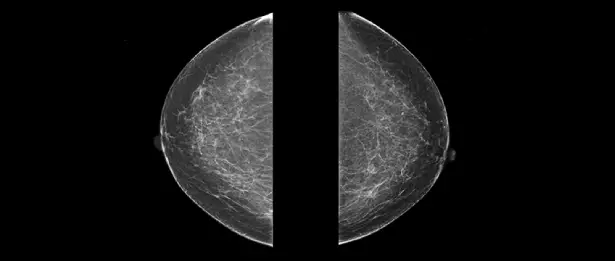

MRI Artifact Considerations With Breast Markers

It’s crucial to understand how breast markers impact MRI artifacts. When a patient with a breast marker gets an MRI, the marker can lead to image quality issues.

What Are MRI Artifacts?

MRI artifacts are distortions or anomalies seen on MRI images. They can be caused by patient movement, machine problems, or materials like breast markers. These issues can make MRI results less reliable.

How Breast Markers Affect Image Quality

Breast markers can distort MRI images because of their material. The severity of these distortions depends on the marker’s type and the MRI sequence used. For example, markers made from metals can create big signal voids or distortions.

The type of breast marker used is key in determining how much it affects MRI images. Markers made from titanium or stainless steel have different effects. Knowing these differences is important for reducing artifacts and improving diagnostic accuracy.

Techniques to Minimize Artifacts

There are ways to lessen MRI artifacts from breast markers. Changing the MRI sequence or using special protocols can help. Also, picking an MRI-compatible breast marker can greatly reduce artifact problems.

Radiologists and MRI technicians have strategies to improve image quality. They can use artifact-reducing sequences or adjust the MRI scan’s orientation. This helps lessen the marker’s impact on the image.